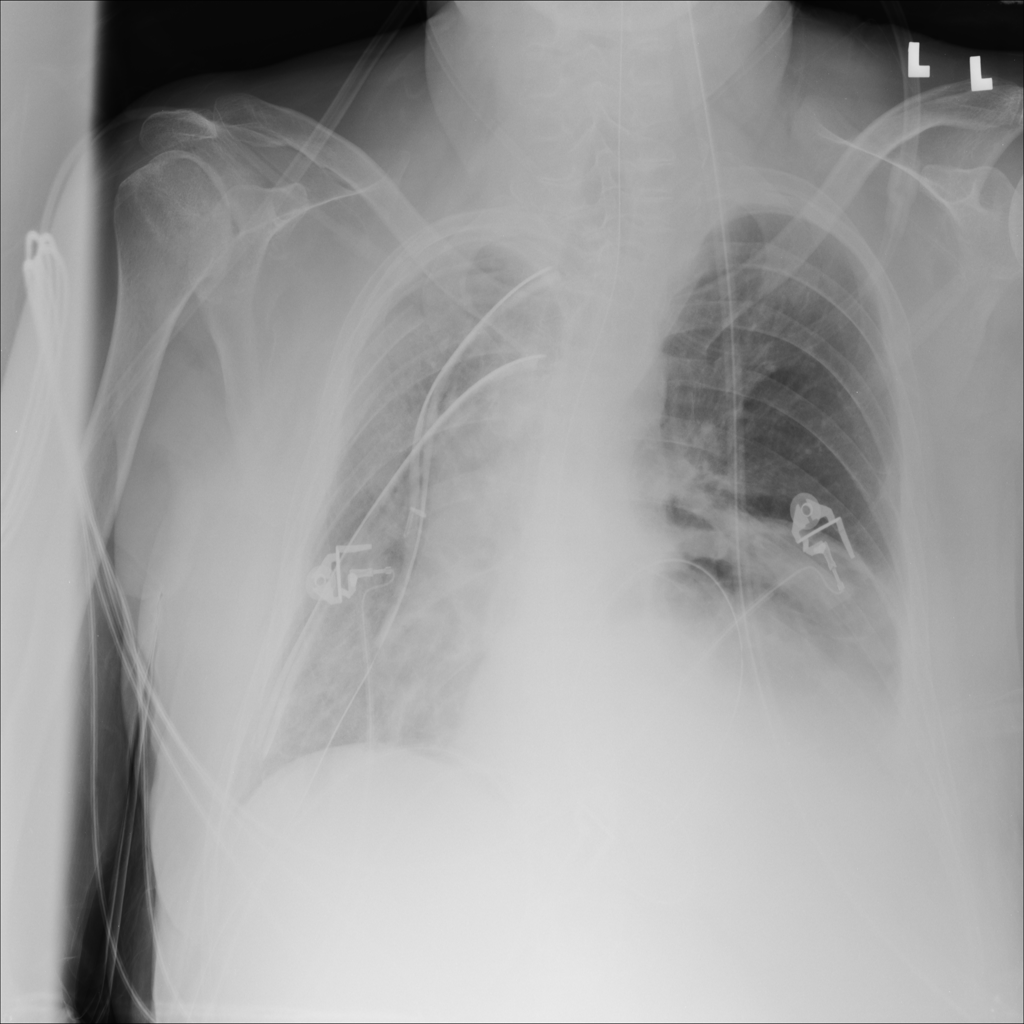

PAT-C048 · IMG-000Hernia

PAT-C048 · IMG-000

PA